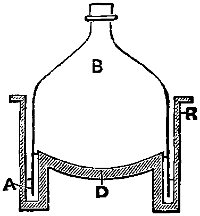

| Williams’ Apparatus for Investigating Action of Poisons on the Frog’s Heart, | 44 | |